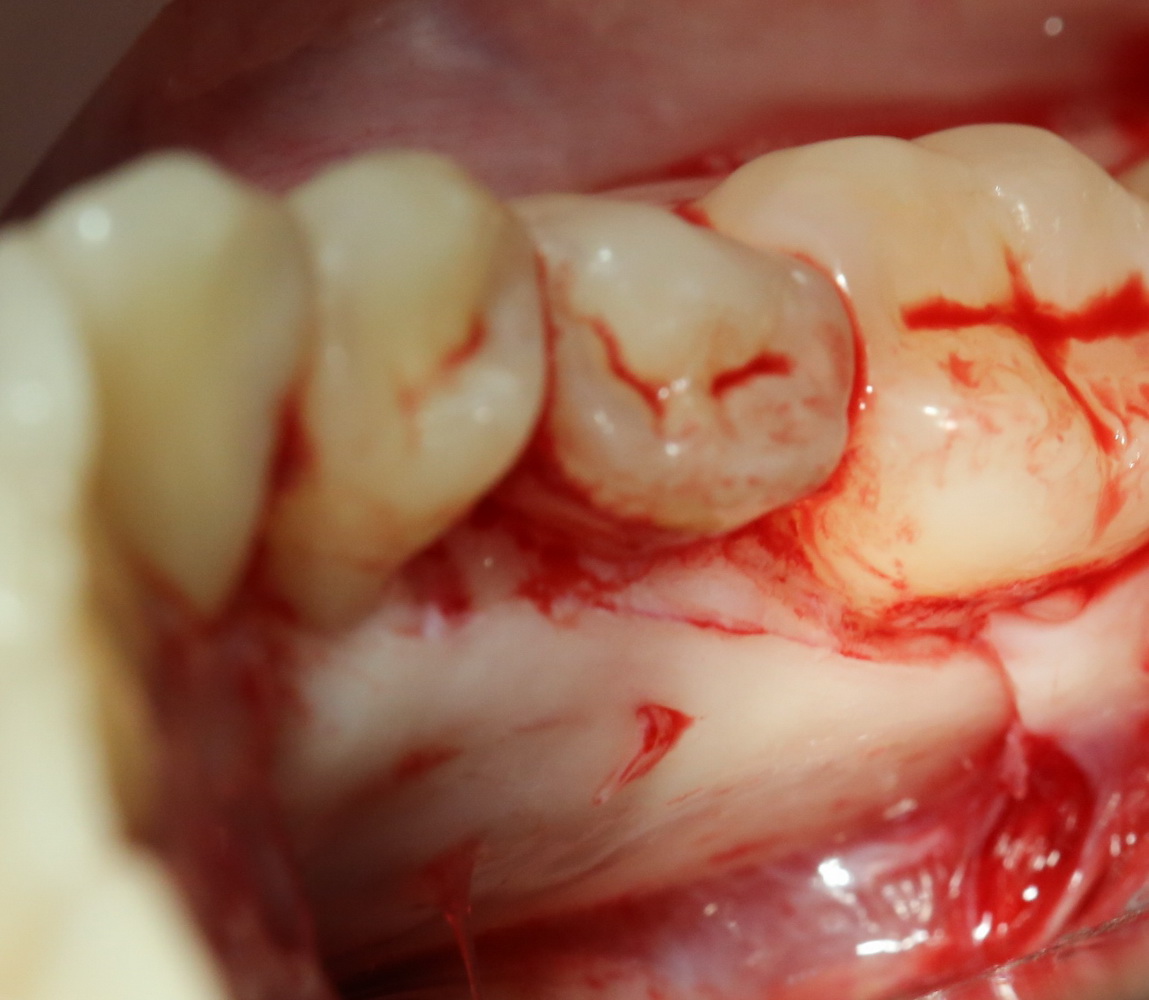

Костная «дверца» на время отделяется и убирается в физраствор, а мы видим следующее:

Это фолликулы и, частично, коронковые части сверхкомплектных зубов.

Теперь аккуратно нам нужно выделить сами зубы:

А вот они! Далее мы руководствуемся главным правилом хирурга-стоматолога:

При удалении зубов нельзя прилагать значительных физических усилий. Если операция идет правильно, зубы должны, вообще, сами вываливаться из лунок.

Однако, наши сверхкомплектные зубы вываливаться не хотят. Потому что их коронки образуют что-то вроде клина, который непросто вытащить через маленькое трепанационное отверстие.

Поэтому мы, всё также, с помощью ультразвука, отпиливаем коронку одного из зубов:

После чего, зубы вываливаются из лунок самостоятельно. В прямом смысле слова: